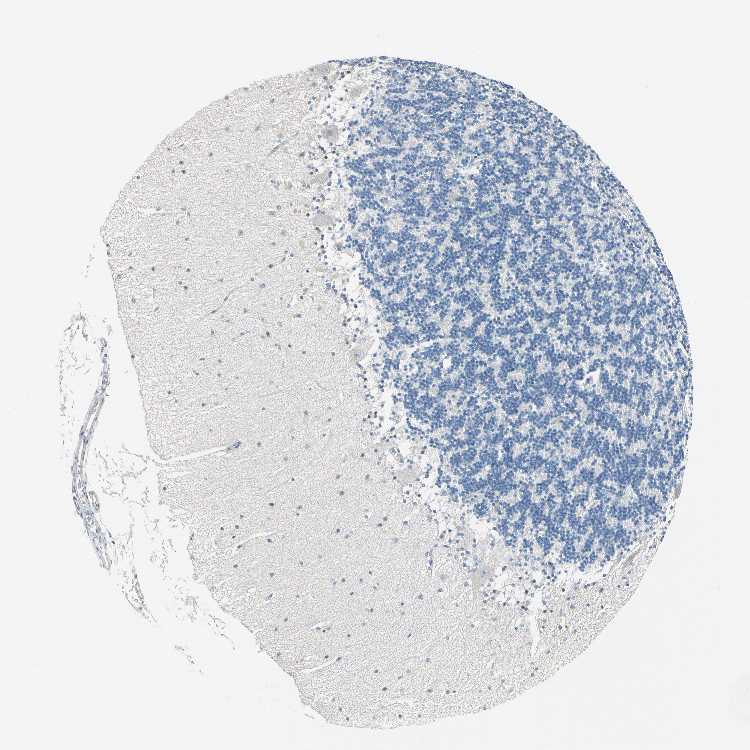

CEREBELLUM - Antibody stainingi

Antibody staining in the annotated cell types in the current human tissue is reported as not detected, low, medium, or high, based on conventional immunohistochemistry profiling in selected tissues. This score is based on the combination of the staining intensity and fraction of stained cells.

Each image is clickable and will lead to virtual microscopy that enables deeper exploration of all samples and also displays staining intensity scores, fraction scores and subcellular localization as well as patient and tissue information for each sample.

Antibody HPA008026

Purkinje cells Not detected

Cells in granular layer Not detected

Cells in molecular layer Not detected